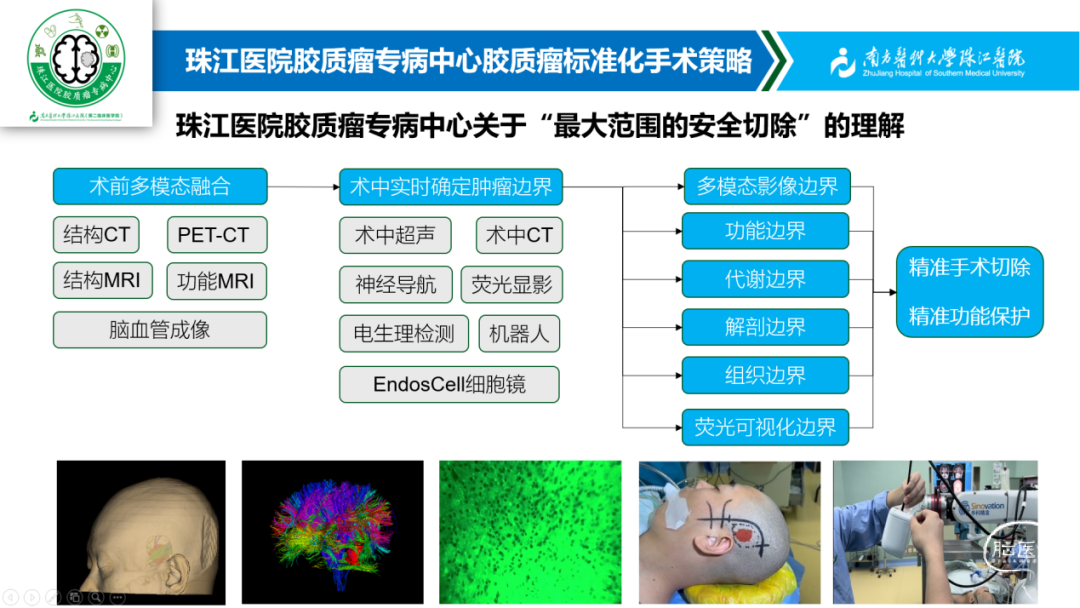

多模态影像评估和引导下脑内肿瘤的精准手术切除及机器人活检,此技术作为微侵袭神经外科的一种精准诠释,它结合了多模态影像评估、精准手术切除和机器人活检等多个方面,为脑内肿瘤的治疗提供了更为精准、安全和有效的手段,这项技术不仅提高了肿瘤的全切率,还降低了手术风险和并发症的发生率,改善了患者的生存质量。同时,机器人活检技术的引入也为脑内肿瘤的病理诊断提供了更为便捷和准确的手段。

胶质瘤是神经外科最常见的颅内原发性恶性肿瘤,其治疗手段包括手术、放疗、化疗、电场治疗等。手术是迄今治疗胶质瘤最有效的手段,但为了巩固手术效果,术后常需要结合放疗、化疗和电场治疗。故此,我院成立胶质瘤专病中心,此专病中心为国家级胶质瘤规范诊疗示范基地,其整合多学科力量,旨在为每位胶质瘤患者带来一种综合、个体化的治疗方案,提高患者的治疗效果和生活质量。